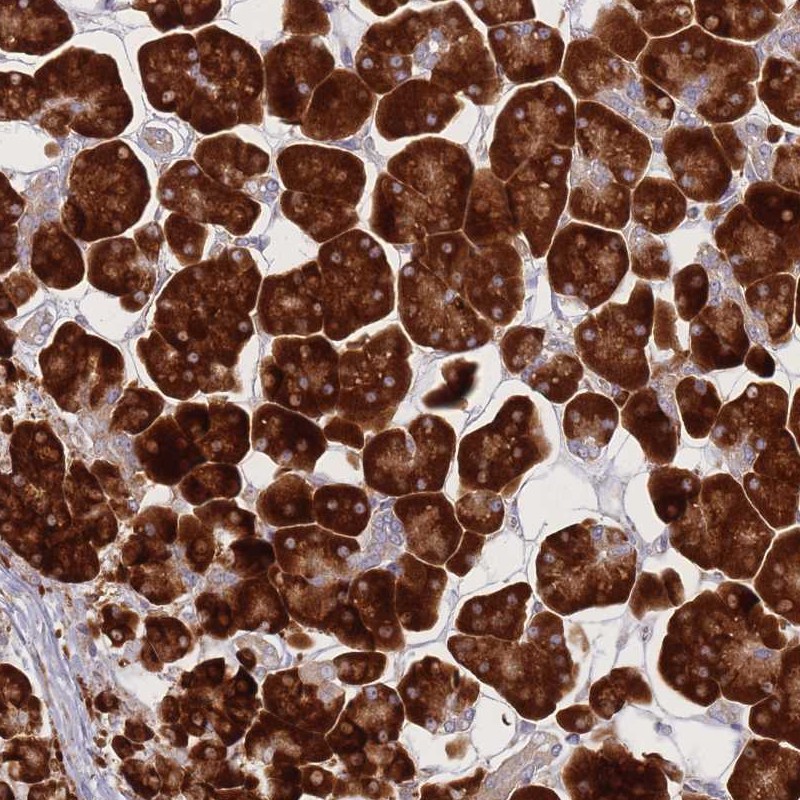

Immunohistochemical staining of human pancreas shows strong cytoplasmic positivity in exocrine glandular cells.